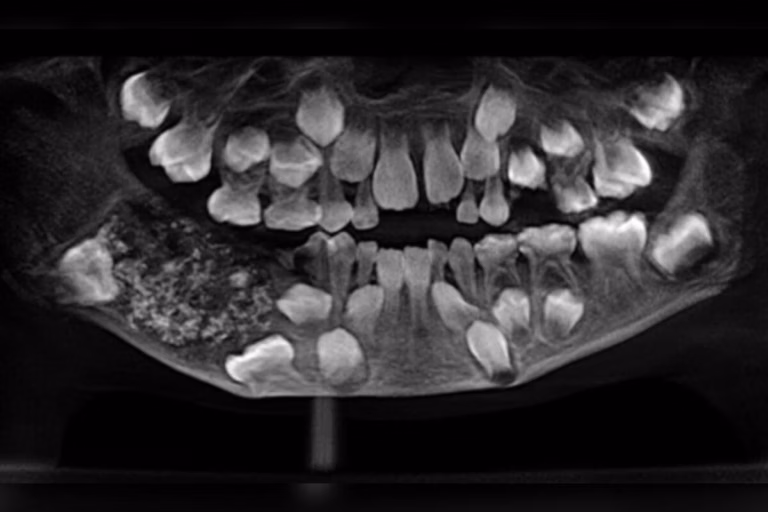

Um caso que parecia apenas um simples inchaço no maxilar se transformou em um marco da odontologia mundial. Em 2019, médicos do Saveetha Dental College and Hospital, em Chennai, na Índia, retiraram 526 dentes minúsculos da mandíbula de um menino de 7 anos.

A cirurgia retirou uma massa de cerca de 200 gramas. Dentro dela, os médicos encontraram uma espécie de bolsa fechada que continha centenas de dentes em miniatura, com tamanho entre 1 e 15 milímetros.

“Foi como abrir uma verdadeira caixa de Pandora. Cada fragmento tinha coroa, esmalte e até raiz, como um dente completo”, relatou a equipe médica em comunicado.

O procedimento durou cinco horas, exigindo busca minuciosa para a retirada de todos os fragmentos sem comprometer a estrutura mandibular da criança.

Segundo especialistas, este é o primeiro caso documentado no planeta com tantos dentes encontrados em um único paciente. O menino se recuperou bem após a cirurgia, sem necessidade de reconstrução óssea.